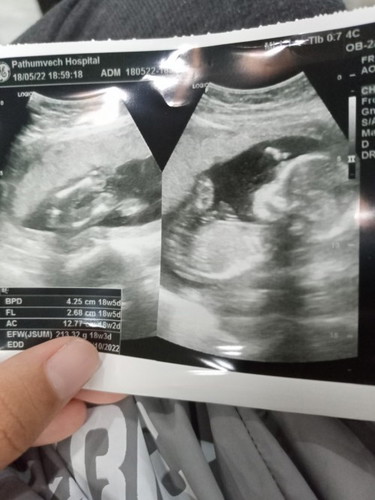

พอดีเราไปอัลตร้าซาวด์มาหมอบอกน่าจะผู้หญิง 50% ถ้าเป็นแบบนี้แม่ๆท่านไหนมีประสบการณ์บ้างคะและแบบนี้เป็นผู้หญิงหรือเป็นผู้ชายคะ

หญิงค่ะ ถ้าชายสังเกตรูปฝั่งซ้ายจะมีจู๋ออก แต่นี่เรียบ บ้านนี้ก็เป็นเหมือนภาพฝั่งซ้ายค่ะ ลูกสาว

น่าจะผู้หญิงนะค่ะ ของเราก็ได้ภาพคล้ายๆแบบนี้เป็นน้องผู้หญิง

พึ่ง18วีคเองรอดูไปเรื่อยๆนะคะยิ่งโตยิ่งเห็นชัดคะ